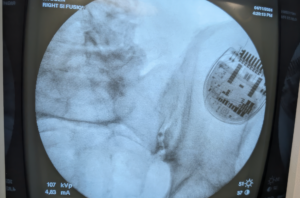

Dr. Quang Nguyen utilizes iFuse INTRA X® allografts for the percutaneous treatment of an active female farmer's SI joint dysfunction.